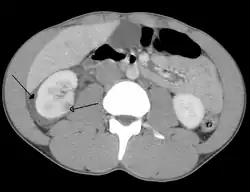

Traumatisme abdominal résultant en la contusion du rein droit (flèche vide) et du sang entourant le rein en question (flèche pleine).